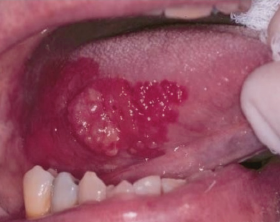

También llamada Medicina Bucal, es la rama de la odontología que se encarga del diagnóstico y manejo de las enfermedades propias de la boca y de las enfermedades sistémicas (de otros sitios del organismo), que tienen manifestaciones bucales.

• El cáncer oral, el diagnóstico y tratamiento quirúrgico de la lesión y la rehabilitación con la somato prótesis. También se encarga del manejo de las implicaciones o consecuencias de la radioterapia y quimioterapia.

El estomatólogo hace parte de un equipo de salud y está en la capacidad de diagnosticar patologías infecciosas, tumorales y de malformación, tomar biopsias y realizar tratamientos de urgencias, de síndromes dolorosos y disfunciones miofaciales y de la articulación temporo mandibular (ATM).